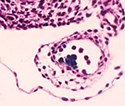

First, the researchers inactivated the gene that codes for the protein Runx1 in the endothelial cells of mouse embryos. During development, some endothelial cells express Runx1, signaling the production of grapelike clusters of HSCs along the interior walls of several major blood vessels. Upon release from the vessel walls HSCs enter the blood circulation and travel to the fetal liver, and upon birth they relocate to the bone marrow.